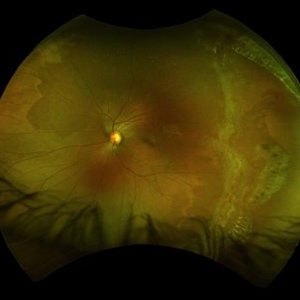

Congenital Hypertrophy of the Retinal Pigment Epithelium Wide Field Optomap

Sep 24 2019 by Sophia El Hamichi, MD

A 52-year-old female followed for 2 temporal lesions of CHRPE OD and white without pressure.

Photographer: Sophia El Hamichi,MD, Murray Ocular Oncology and Retina, Miami

Condition/keywords: congenital hypertrophy of the retinal pigment epithelium (CHRPE), Optomap, ultra-wide field imaging, white without pressure